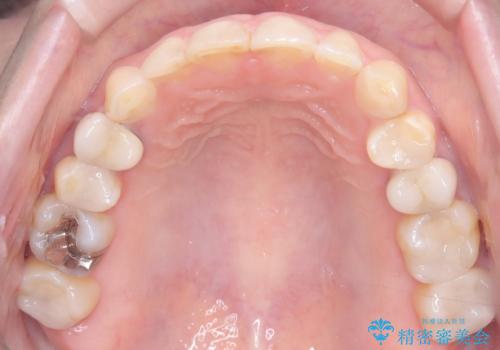

- 下の前歯のデコボコ(叢生)を気にされてご来院されました。精密な検査の結果、下の前歯を並べるスペースが不足していることが判明。患者様のご希望から、透明で目立ちにくい**インビザライン(マウスピース矯正)による治療計画を立案しました。主に歯の側面をわずかに削るIPR(歯間乳頭保護下ストリッピング)**などでスペースを確保し、下の前歯の叢生を解消することを目指します。

今回の矯正治療では、透明なマウスピース型の装置インビザラインを使用しました。目立たず、取り外しが可能なため、日常生活にほとんど影響なく治療を進めることができました。治療は、緻密に計算された計画に基づき、IPRなどで必要なスペースを確保しながら、下の前歯をスムーズに移動。これにより、長年の悩みであった下の前歯のデコボコが解消され、清掃しやすい、整った歯並びを獲得していただけました。